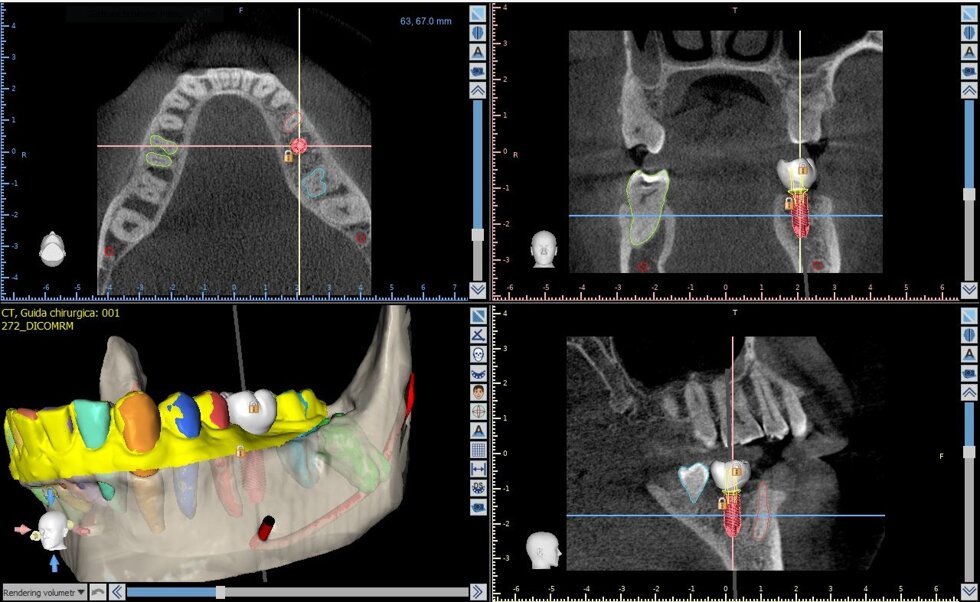

Il processo inizia con una tomografia computerizzata (CBCT), che fornisce un’immagine tridimensionale dettagliata delle arcate dentarie e delle strutture ossee. I dati vengono importati in software dedicati, dove il chirurgo può pianificare virtualmente l’intervento: scegliere la posizione, l’inclinazione e la profondità ottimali di ciascun impianto, valutando anche la densità ossea e la distanza da nervi o seni mascellari.

Una volta definito il piano chirurgico, si procede alla realizzazione di una dima chirurgica personalizzata, ottenuta tramite stampa 3D. Questa mascherina guida gli strumenti del chirurgo durante l’intervento, consentendo di inserire gli impianti nella posizione esatta prevista dal progetto digitale, senza necessità di ampie incisioni gengivali.